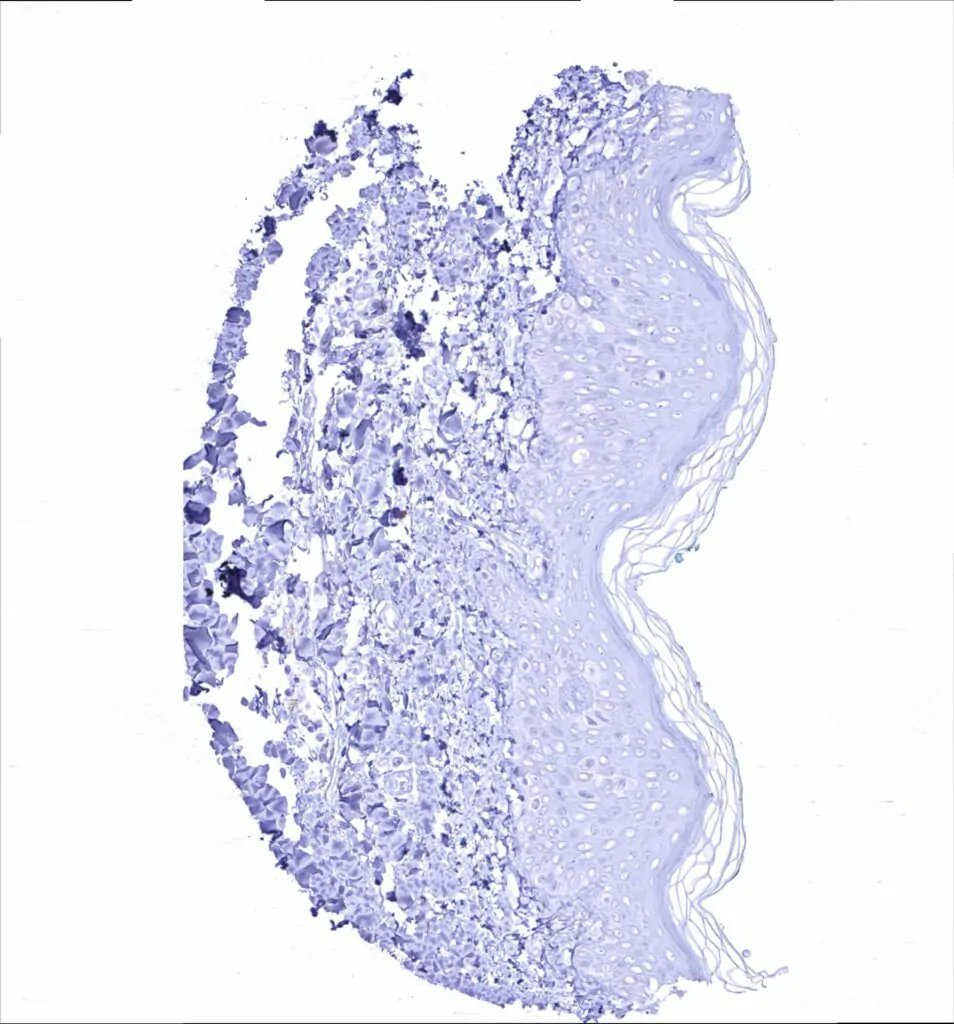

Skin